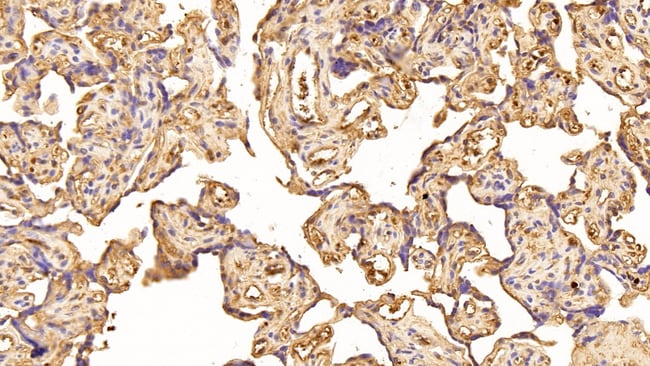

Caspase 1 Polyclonal Antibody for Western Blot, ICC/IF, IHC (P)

| Immunohistochemistry (Paraffin), Western Blot, Immunocytochemistry | |

| Human, Mouse, Pig | |